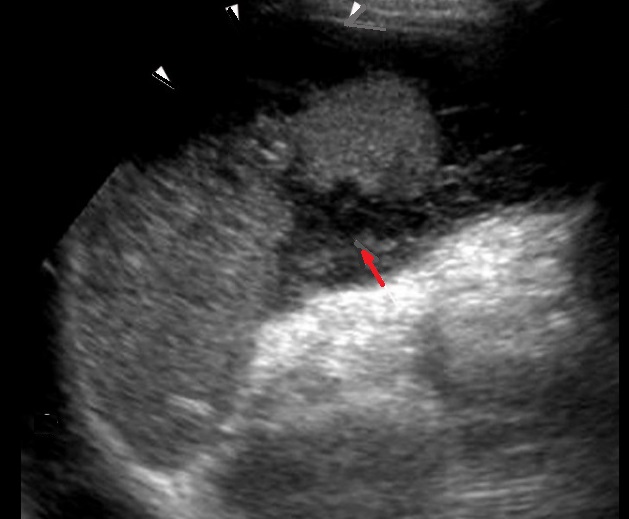

Image

echographique d'une traumatisme de la rate avec

aspect hemoperitoine localiuse peri-hilaire

splenique . |

Image echographique d'une autre

traumatisme de la rate de grade II avec aspect

de laceration casulaire profonde et des hematomes

hypoechogene intra-patenchymateuse .

Complication hemoperitoine peri-capsulaire localise

peut en s,observer ( fleche blanche ) |